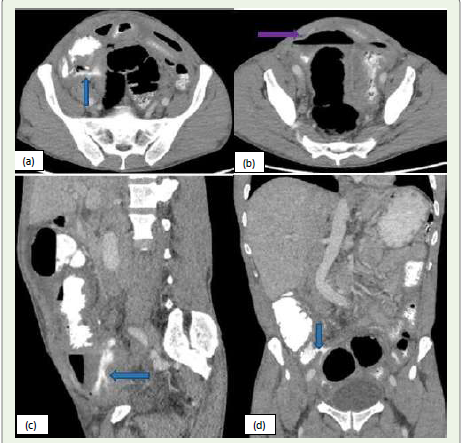

Figure 5: (a, b, c, d):Sagittal, Axial and coronal CT images of a 57-year-old

male patient presents with lower abdominal pain. CT scan of abdomen and

pelvis with oral and IV contrast shows extra-luminal extravasation of oral

contrast adjacent to the ileocecal junction forming a focal collection with air

fluid level in right lower quadrant of the abdomen (blue arrow), suggestive

of anastomotic leak. Additionally, there is formation of another Extraluminal

collection with air-fluid level (purple arrow) is also seen in the pelvis

suggestive of complications.